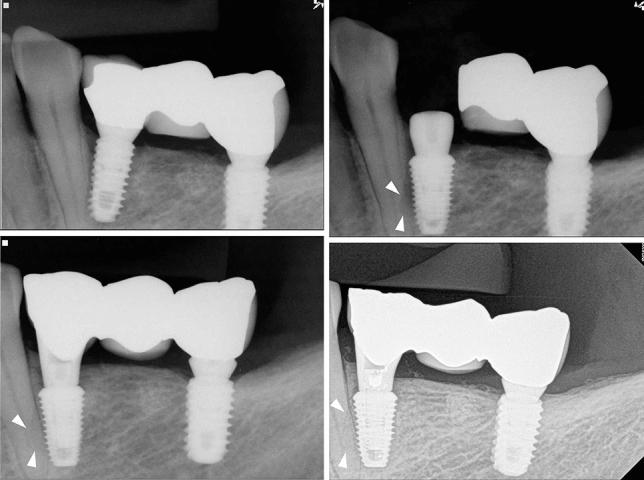

The purpose of the retrospective study was to investigate the long-term result of implant-induced injury on the adjacent tooth. The subjects of this retrospective study were patients who had received implants and had tooth injury; direct invasion of root (group I), root surface contact (group II), or < 1 mm distance of the implant from the root (group III). Clinical and pathological changes were periodically examined using radiographs and intra-oral examinations. Paired t-tests and chi-square tests were used to evaluate the implant stability quotient (ISQ) of implant and tooth complications, respectively (α = 0.05). A total of 32 implants and teeth in 28 patients were observed for average 122.7 (± 31.7, minimum 86) months. Seven teeth, three of which were subsequently extracted, needed root canal treatment. Finally, 90.6% of the injured teeth remained functional. Complications were significant and varied according to the group, with group I showing higher events than the others. The ISQs increased significantly. One implant in group I resulted in osseointegration failure. The implant survival rate was 96.9%. In conclusion, it was found even when a tooth is injured by an implant, immediate extraction is unnecessary, and the osseointegration of the invading implant is also predictable.

摘要

这项回顾性研究的目的是调查种植体对邻牙造成损伤的长期结果。该回顾性研究的对象是接受过种植体植入且存在牙齿损伤的患者;包括牙根直接受侵(I组)、牙根表面接触(II组)或种植体与牙根距离<1mm(III组)。通过X线片和口腔内检查定期观察临床和病理变化。分别采用配对t检验和卡方检验评估种植体的种植体稳定性商数(ISQ)和牙齿并发症(α=0.05)。共观察了28例患者的32颗种植体和牙齿,平均观察时间为122.7(±31.7,最短86)个月。7颗牙齿需要进行根管治疗,其中3颗随后被拔除。最后,90.6%的受伤牙齿仍保持功能。并发症明显且因组而异,I组的并发症发生率高于其他组。ISQ值显著增加。I组中有1颗种植体发生骨结合失败。种植体存活率为96.9%。总之,研究发现即使牙齿受到种植体损伤,也无需立即拔除,侵入性种植体的骨结合情况也是可预测的。